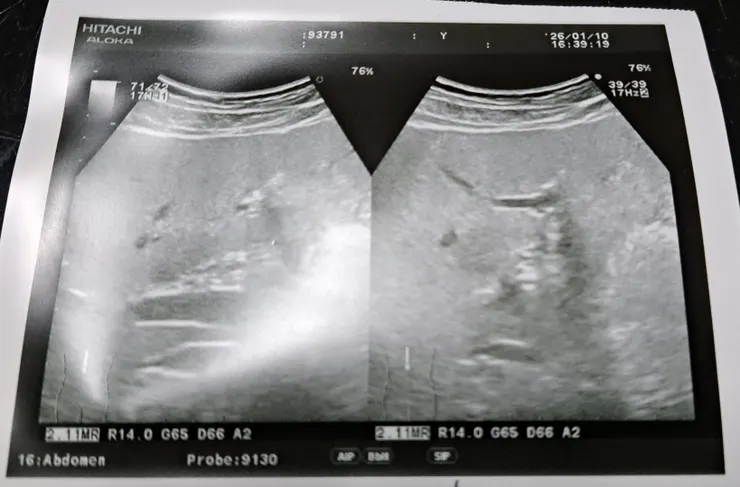

去年家庭醫師為我做了超音波,發現了明顯的腫瘤。

在20250118的「長壽佛供養迴向」結壇的禪修中,我的腰部就像浸潤在「氣泡浴池」裡,「波波波波」的,我「看見」自己的腫瘤縮小了。

接著,0122前往台大做了斷層掃描,昨天看了報告。

「肝臟只有小於一公分的水泡,無腫瘤。」